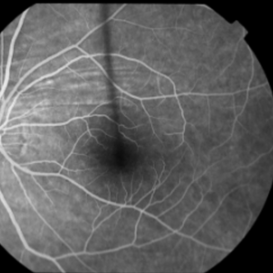

This 53 year old man was noted to have choroidal folds right greater than left. The visual acuity was normal at 20/15 bilaterally. The intraocular pressure was normal. The choroidal folds are visible on OCT, especially on the vertical cuts that image across the horizontal folds. Angiography revealed staining of the folds without CNVM, choroidal mass, or optic nerve edema. B scan did not reveal any retrobulbar masses. Choroidal folds can be due to hypotony, choroidal masses or retrobulbar masses, inflammatory conditions, choroidal neovascular membranes, optic nerve edema, scleral buckles, and idiopathic. In this case, they were thought to be idiopathic.

This 53-year-old man was noted to have choroidal folds right greater than left. The visual acuity was normal at 20/15. The choroidal folds are visible on OCT, especially on the vertical cuts that image across the horizontal folds. Angiography revealed staining of the folds without CNVM, choroidal mass, or optic nerve edema.